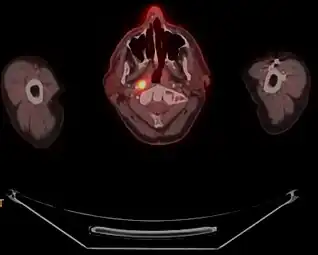

a) Axial PET/CT image reveals a FDG-avid mass in the nasopharynx in keeping with a known nasopharyngeal carcinoma b)axial CECT image shows the infiltrative nasopharyngeal carcinoma c) axial T2W MR image demonstrates the infiltrative nasopharyngeal carcinoma